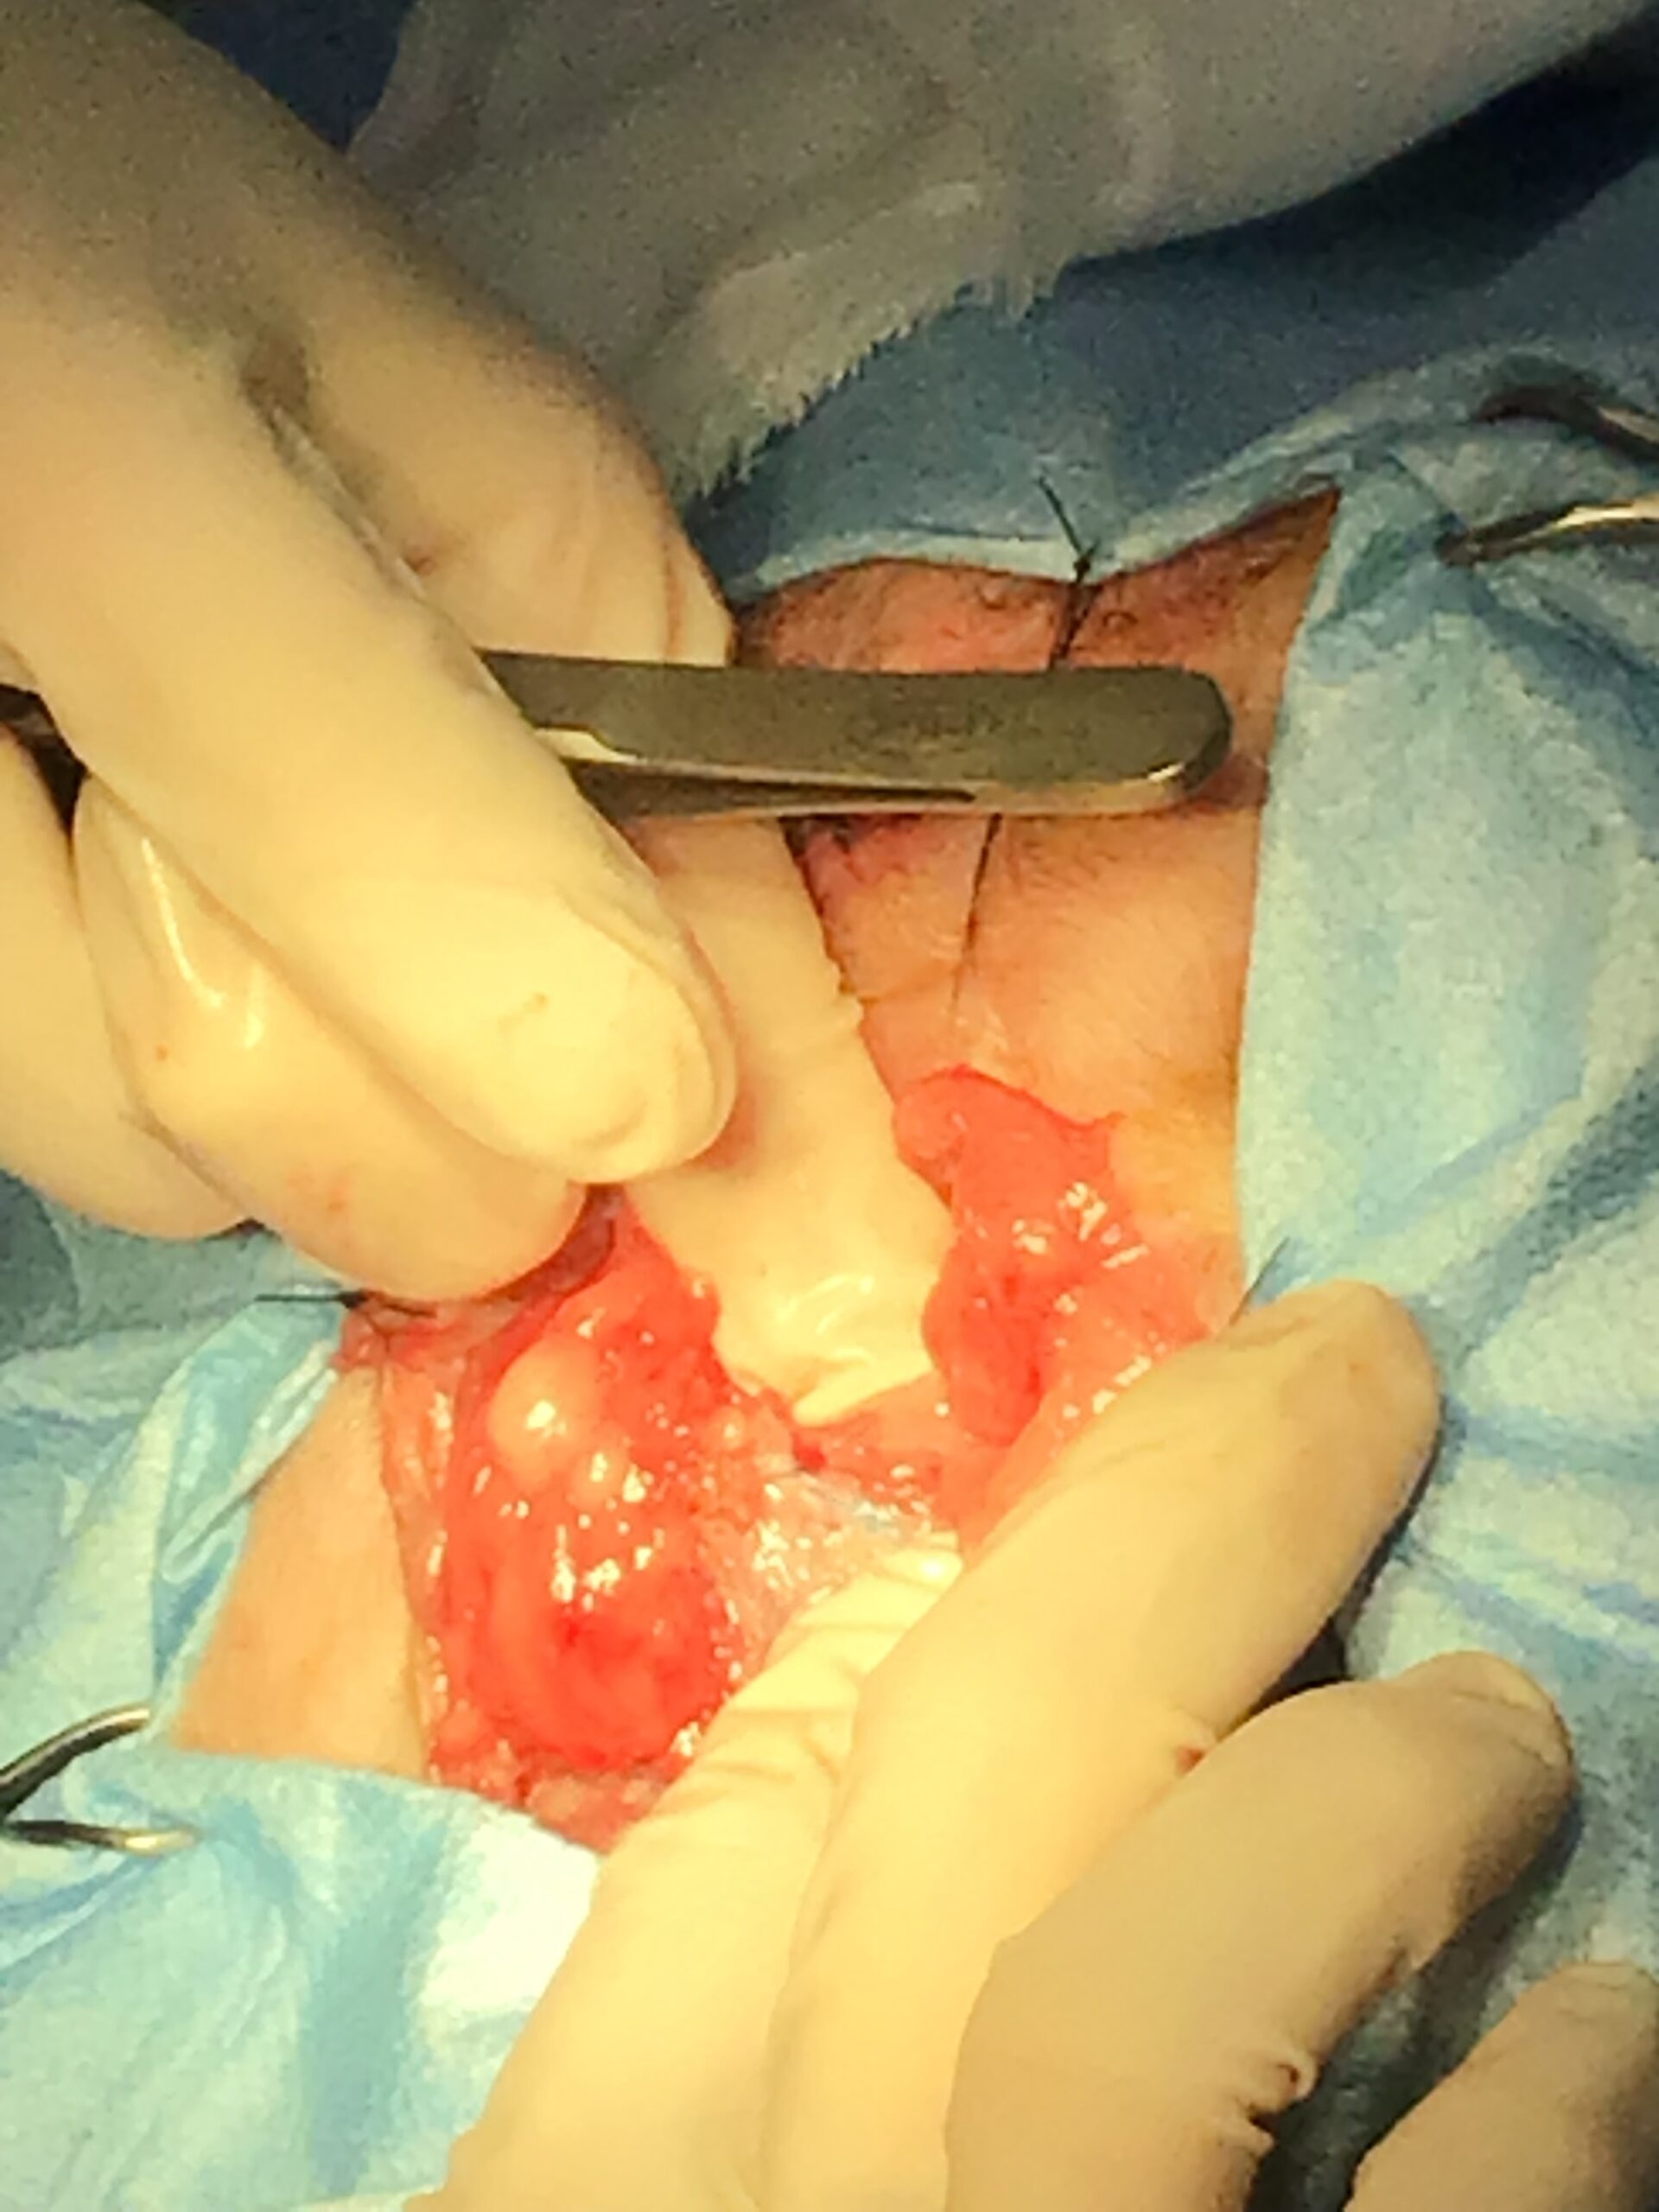

本症例には、時期を分けて2つの大きな外科的介入を行いました。

加えて、会陰ヘルニアの根本的な発症要因となる「前立腺肥大」を退縮させ、将来的な再発リスクを低下させるために、去勢手術も同時に実施しました。

【致死的合併症】メッシュ縫合時に坐骨神経を巻き込んだ場合、術直後から後肢の永久的な神経麻痺(ナックリング)が生じ、直ちに再手術が必要です。また、メッシュへの重度感染や、直腸・前立腺の損傷による化膿性腹膜炎は致死的となります。

This post details our surgical and medical approach to a complex case involving recurrent severe perineal hernia and a malignant liver lymphoma in a senior dog. We emphasize the grim reality of untreated conditions and the severe risks of anesthesia when underlying heart and respiratory diseases are present. To maximize safety, we exclusively use local infiltration anesthesia. Due to a lack of available autologous tissue, a polypropylene mesh and extensive organ pexy (both colon and bladder fixation to the abdominal wall) were required to prevent fatal urethral obstruction and re-herniation. Additionally, simultaneous castration was performed to shrink the enlarged prostate, a key factor in hernia development, thereby reducing the risk of recurrence. For the liver tumor, given its deep location at the liver base and the high risk of fatal bleeding, we opted for a biopsy which confirmed lymphoma. Unfortunately, the patient’s elevated bilirubin and the family’s preference for a compromised, single-agent chemotherapy protocol led to early drug resistance. We candidly discuss the harsh realities of end-stage cancer—it is a painful decline characterized by severe cachexia and organ failure that palliative care can only partially ease. Furthermore, we outline our strict early discharge policy (1-3 days), the physical limitations of our unstaffed overnight remote monitoring, and our referral policy for highly specialized surgeries. We believe in providing honest, logical medical facts rather than false hope, ensuring families can make fully informed and responsible decisions.